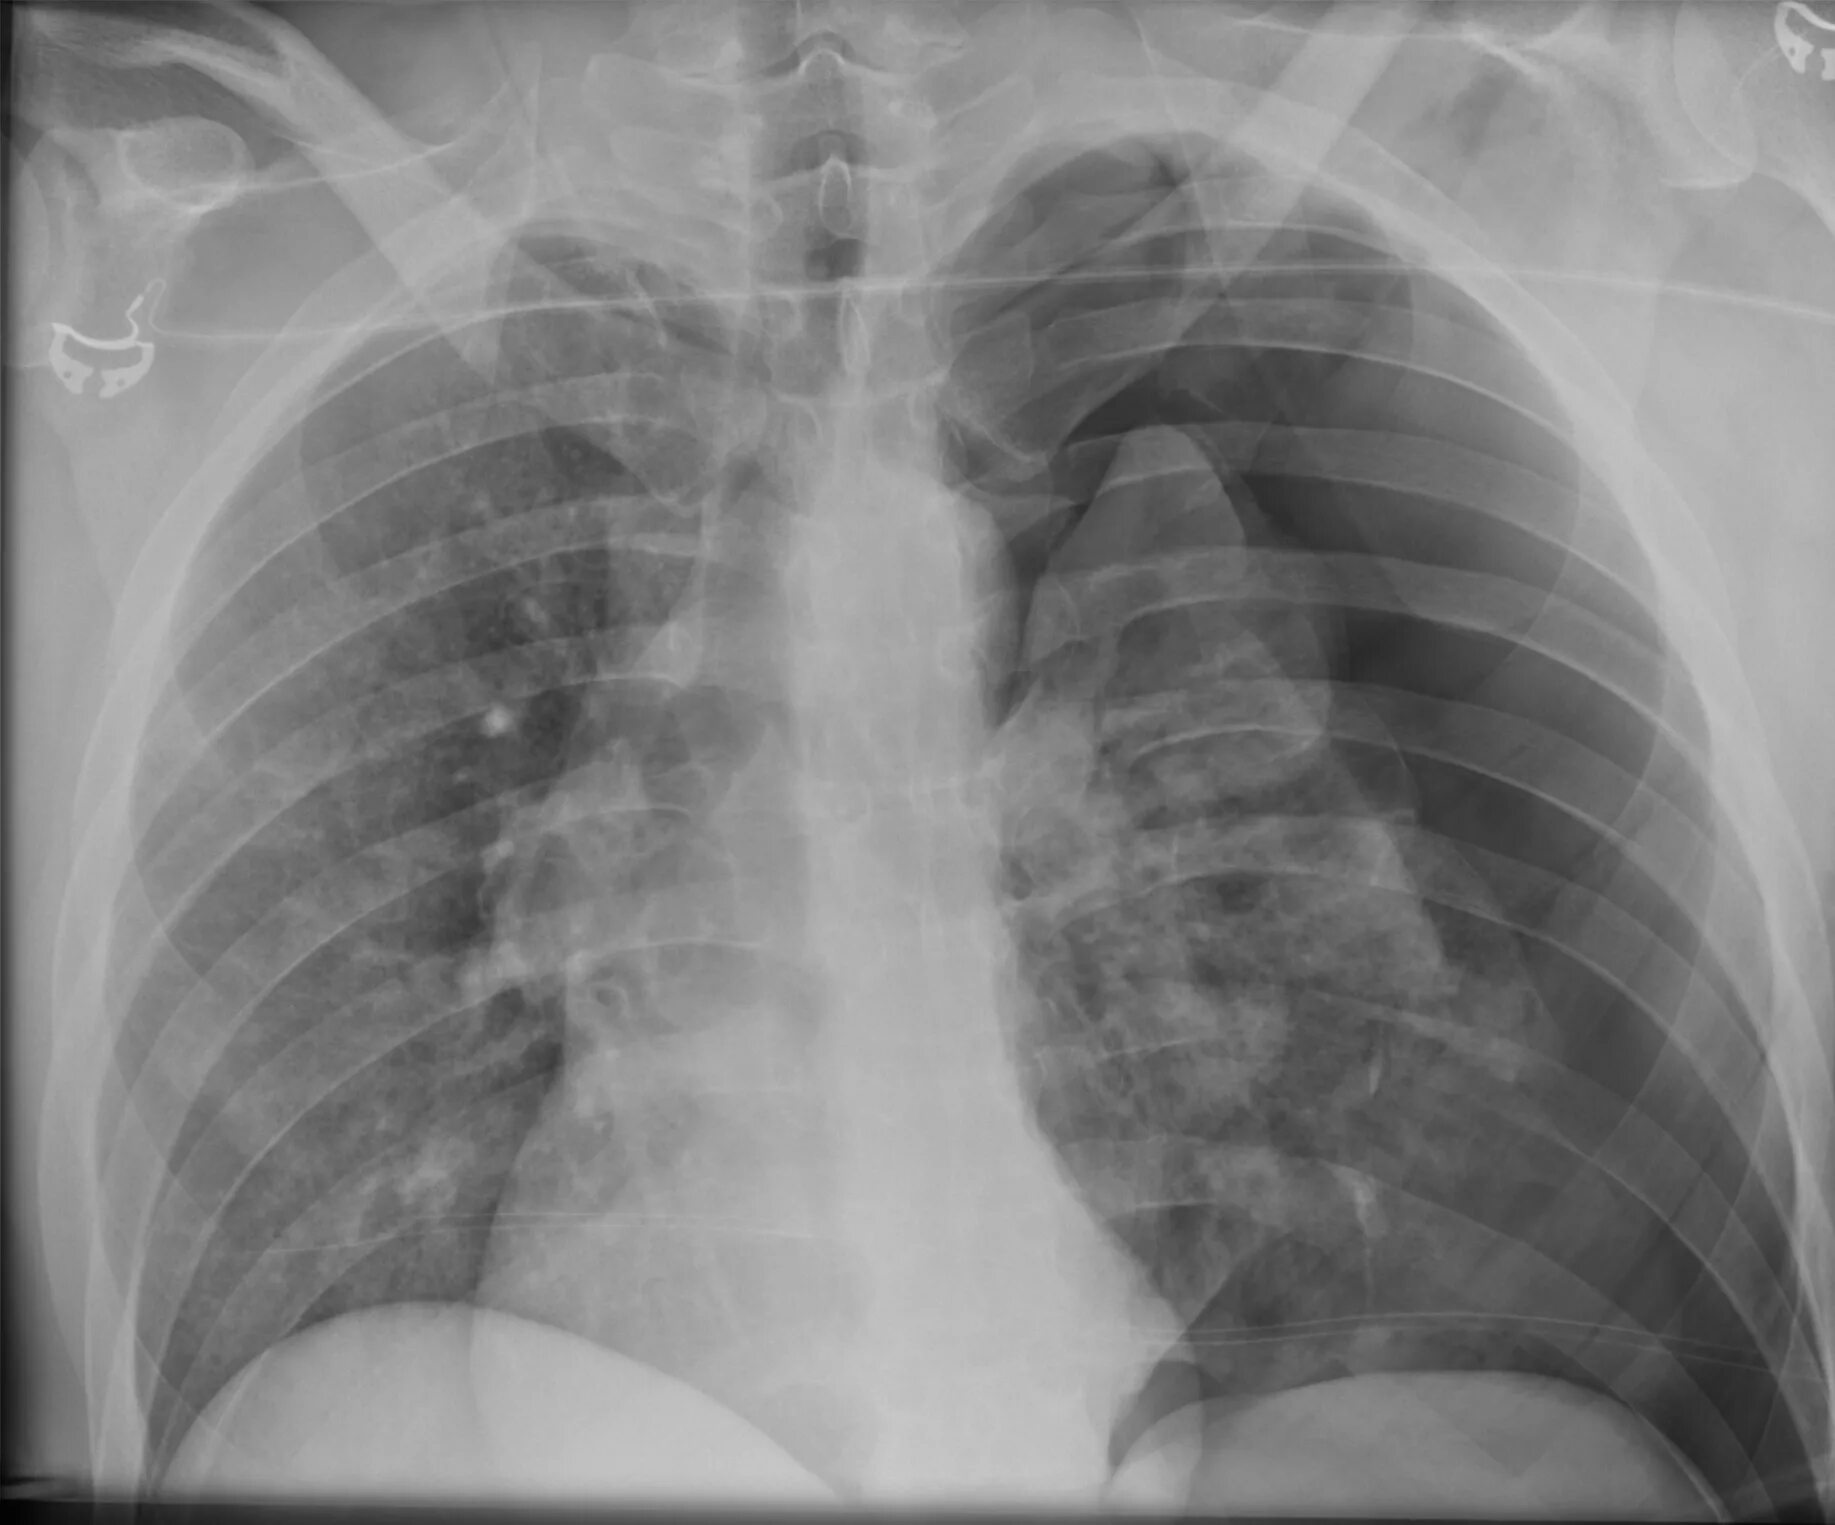

Коллабированное легкое при пневмотораксе